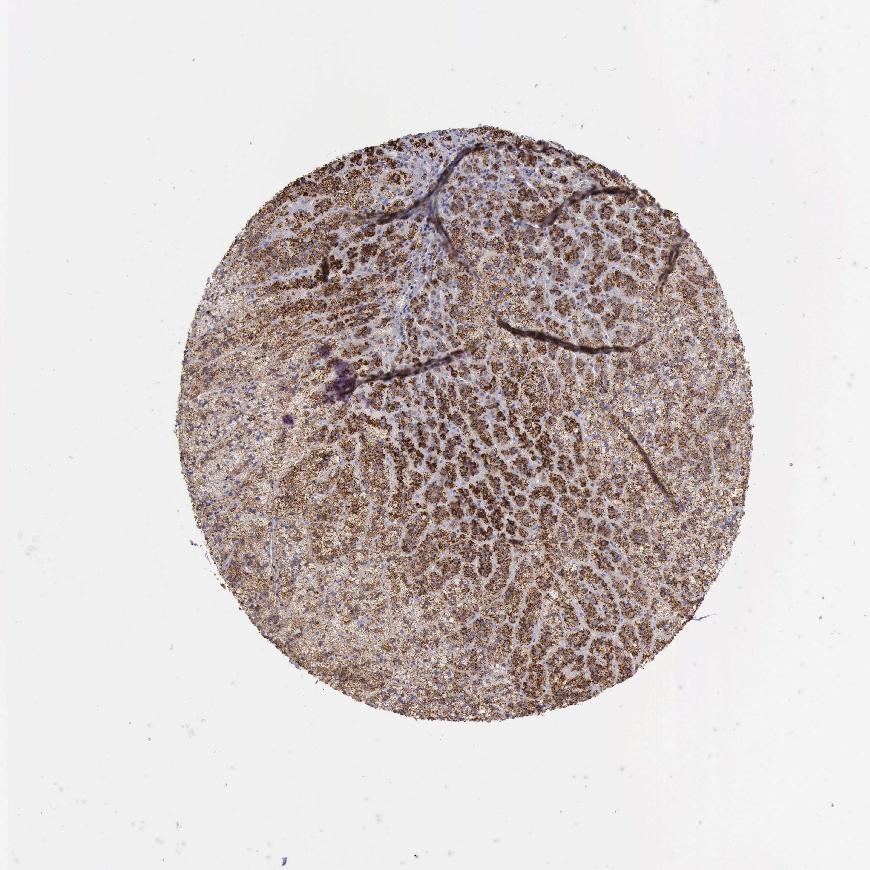

ADRENAL GLAND - Antibody stainingi

Antibody staining in the annotated cell types in the current human tissue is reported as not detected, low, medium, or high, based on conventional immunohistochemistry profiling in selected tissues. This score is based on the combination of the staining intensity and fraction of stained cells.

Each image is clickable and will lead to virtual microscopy that enables deeper exploration of all samples and also displays staining intensity scores, fraction scores and subcellular localization as well as patient and tissue information for each sample.

Antibody HPA000237Antibody HPA000966

Glandular cells HighHigh